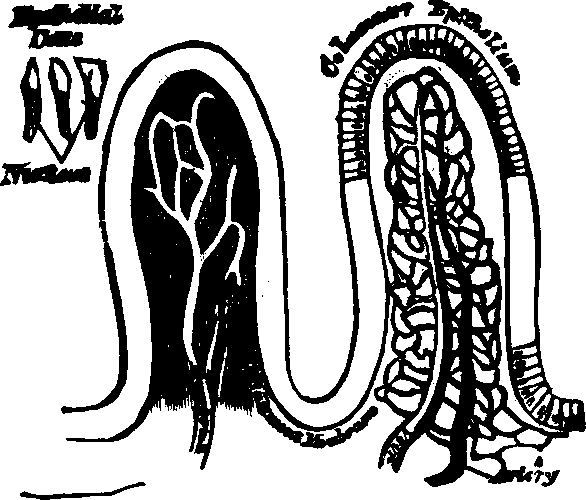

Fig. 30. Villi of the small

intestine greatly magnified.

Fig. 31. A section of the Ileum,

turned inside out, so as to show the appearance and arrangement of the

villi on an extended surface.

Fig. 35. Villi of the small

intestine greatly magnified.

Absorption is the vital function by which nutritive materials are

selected and imbibed for the sustenance of the body. Absorption, like all

other functional processes, employs agents to effect its purposes, and the

villi of the small intestine, with their numberless projecting

organs, are specially employed to imbibe fluid substances; this they do

with a celerity commensurate to the importance and extent of their duties.

They are little vascular prominences of the mucous membrane, arising from

the interior surface of the small intestine. Each villus has two sets of

vessels. (1.) The blood-vessels, which, by their frequent blending, form a

complete net-work beneath the external epithelium; they unite at the base

of the villus, forming a minute vein, which is one of the sources of the

portal vein. (2.) In the center of the villus is another vessel, with

thinner and more transparent walls, which is the commencement of a

lacteal.